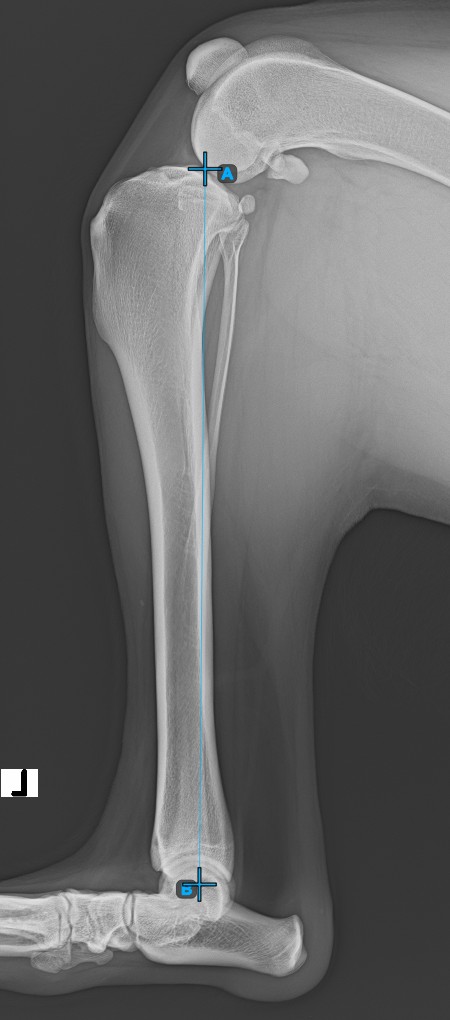

Start the measurement by marking the Eminentia Intercondylaris, which is located on the joint connecting the femur and the tibia.

The image below depicts the usual placement of the Eminentia Intercondylaris point.

Continue by marking the midpoint of the Cochlea, located at the end of the tibial bone. The line created between the Eminentia Intercondylaris and the midpoint of the Cochlea represents the long axis of the tibia.

The image below depicts the usual placement of the midpoint of the Cochlea.